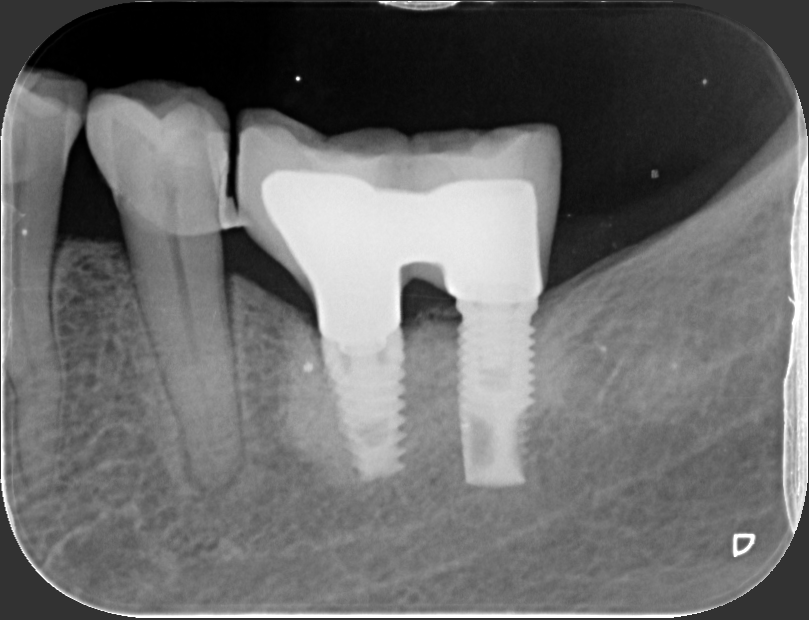

Buenos días compañeros. Necesitamos rehabilitar con transepitelial estos implantes que veis en foto y en RX periapical y desconocemos marca y modelo

Perdona que te pregunte, pero ¿la rx corresponde con la restauración de la foto? Lo digo porque la rx es un puente posterior, y las imágenes es de un unitario anterior. Los de la rx, el posterior es un hexágono externo plataforma RP (4,1), mientras que el mesial parece un hexágono interno compatible, de plataforma 3,5. En otro implante, parece un Eckermann Duplo.

El implante mesial es un duplo como bien dice José Luis y los otros un hexágono interno y otro hexágono externo.

Buenas tardes de nuevo. Pido disculpas, la RX inicial no es correcta. La RX correcta es esta que se corresponde con las fotografías

Lo que te dijimos, Eckermann Duplo.

No sé por qué dijimos Duplo, sería All Espiral, y creo que sólo tiene una plataforma.